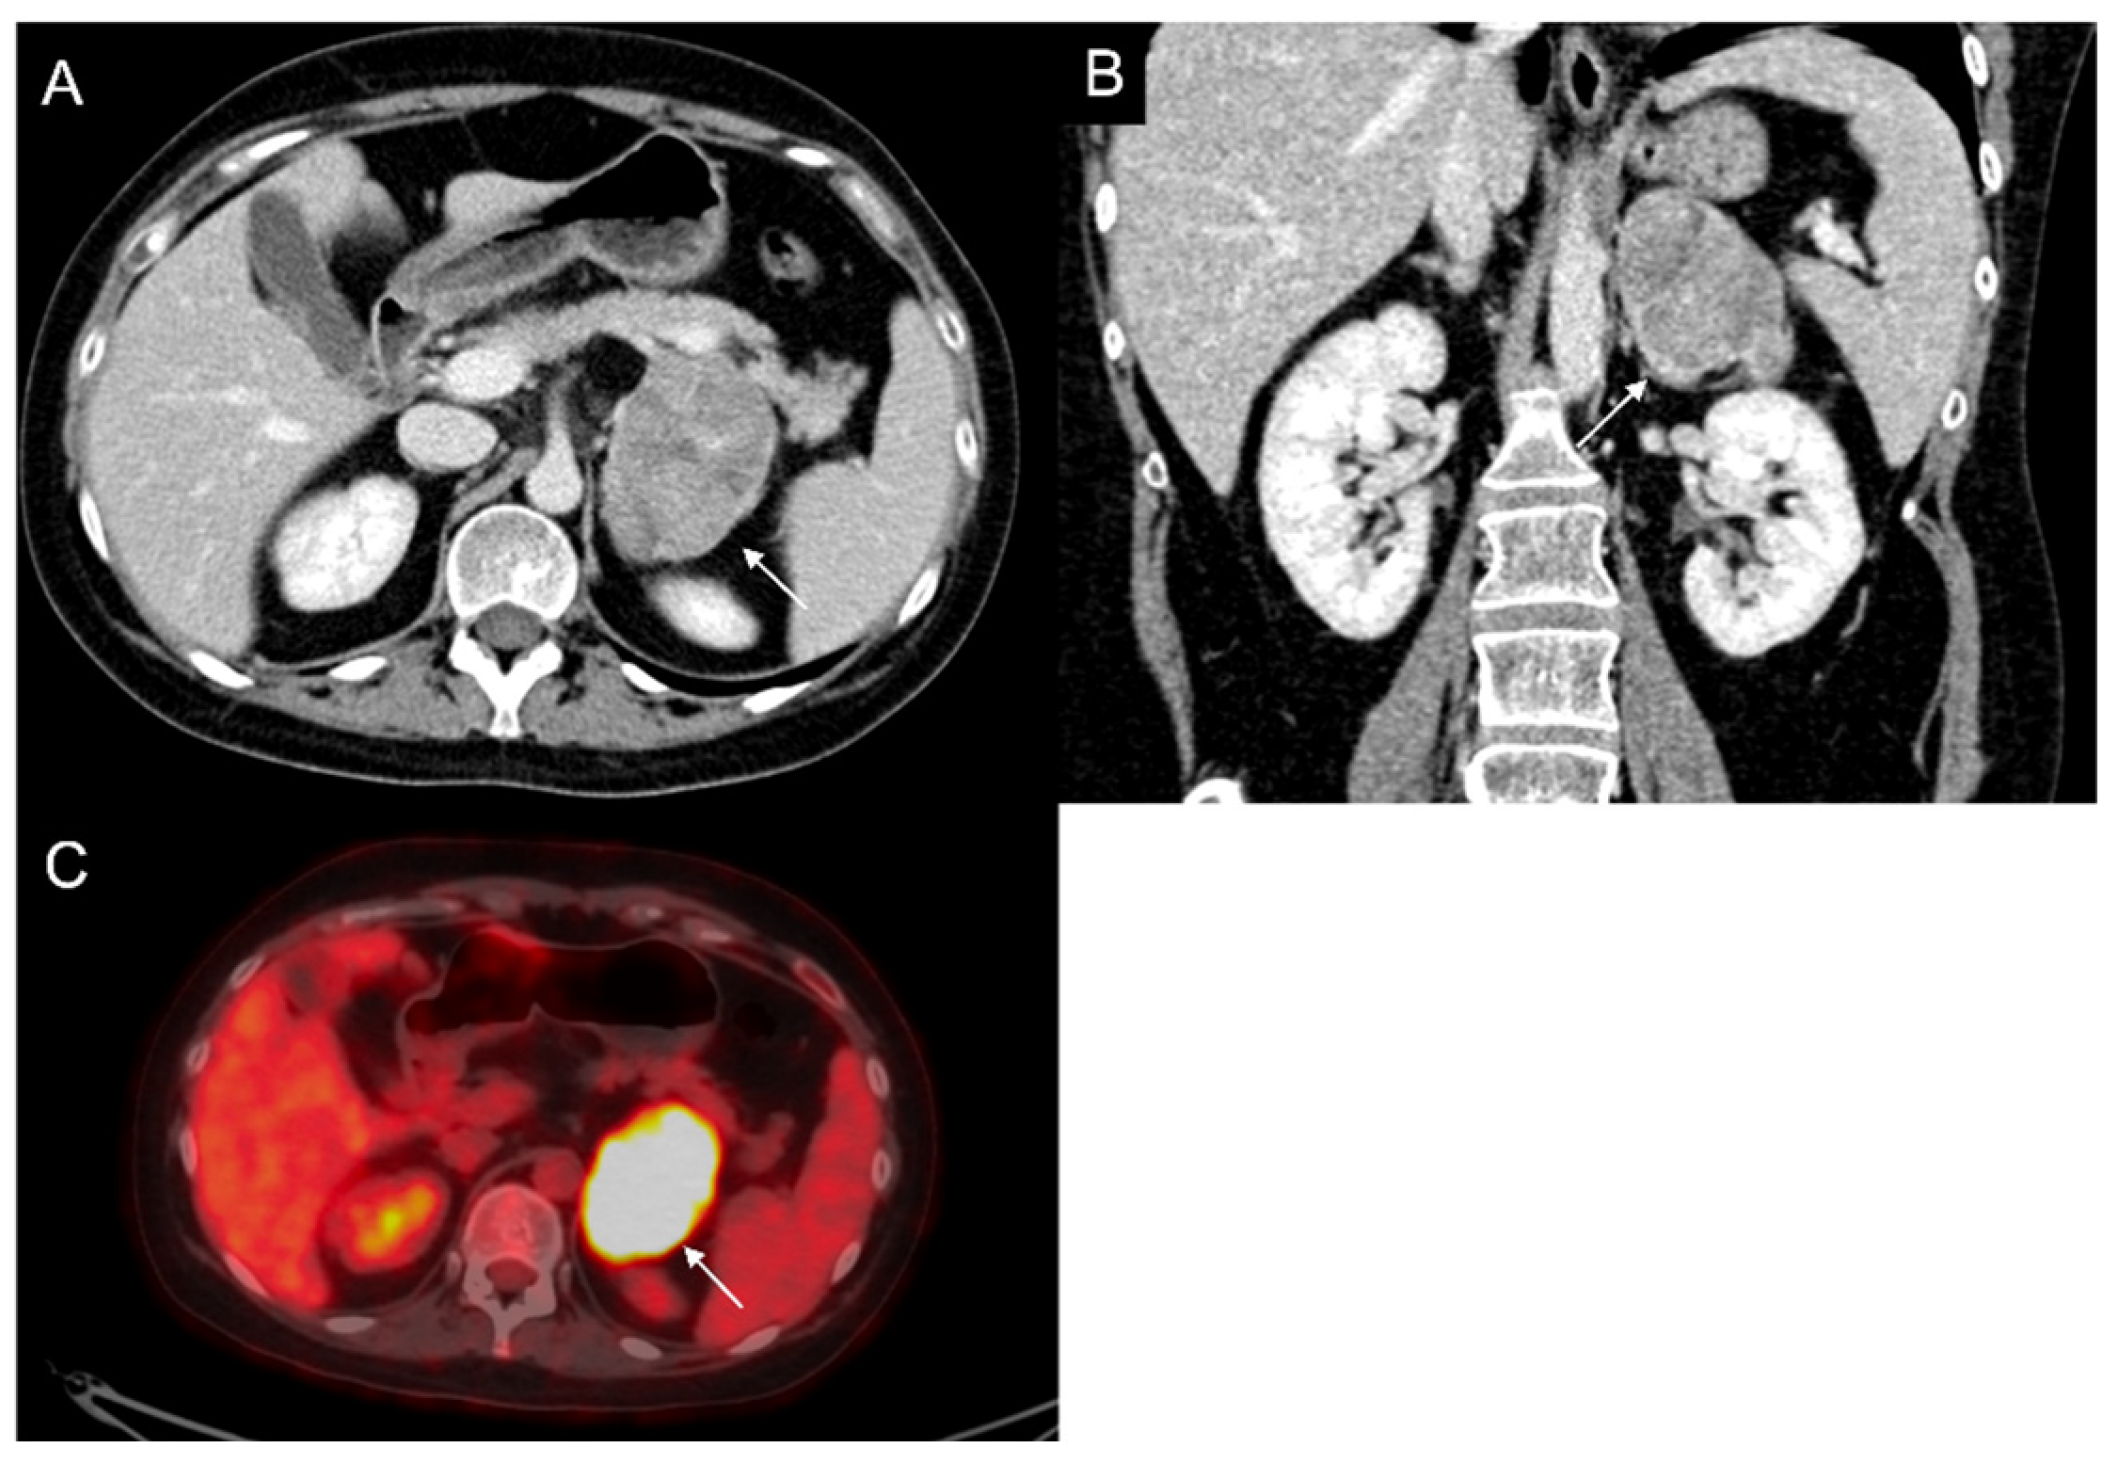

Figure 8.

79-year-old female patient with left adrenal lesion detected at abdominal ultrasound performed for abdominal pain. Homogeneous left adrenal mass with density on non-contrast CT (A) less than 10 HU (6 HU, SD4 HU) and washout (>60%) in the venous (B) and late post-contrast phases (C), compatible with adenoma.

Figure 9.

Voluminous lesion (arrow) of the left adrenal gland measuring 60 × 55 mm with density value > 20 HU on basal CT (A) and inhomogeneous enhancement on venous (B) and late post-contrast phases (C) due to the presence of necrotic and cystic areas. Histological diagnosis of Adrenocortical carcinoma.

Figure 10.

Man 60 years old with left adrenal incidentaloma. Hypodense mass (arrow) without contrast enhancement on CT (A,B), typically benign, stable in follow-up.